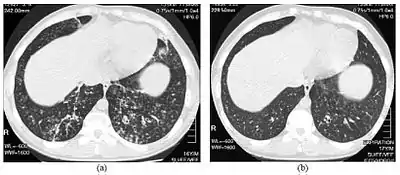

![]() صور تصوير مقطعي محوسب عالي الجودة لأسفل الصدر في ولد عمره 16 سنة مصاب بالتهاب عموم القصيبات المنتشر صور تصوير مقطعي محوسب عالي الجودة لأسفل الصدر في ولد عمره 16 سنة مصاب بالتهاب عموم القصيبات المنتشر | |

يتطلب تشخيص المرض فحص طبي للرئتين ونسيج القصيبات، وهو ما قد يحتاج لخزعة، أو المفضل أكثر تصوير مقطعي محوسب عالي الجودة للرئتين. تشمل المعايير التشخيصية للمرض التهاب شديد في كل طبقات القصيبات التنفسية وإصابات في نسيج الرئة تظهر في شكل عقيدات في القصيبات النهائية والتنفسية في كلا الرئتين. تظهر العقيدات في التهاب عموم القصيبات المنتشر في صورة كتل معتمة عند رؤيتها بالأشعة السينية، وقد تسبب انسداد مجرى الهواء، وهو ما يتم تقييمه بقياس التنفس. تكشف الأشعة السينية كذلك عن اتساع ممرات القصيبات، وهي علامة أخرى للمرض. يُظهر التصوير المقطعي المحوسب عالي الجودة عادة انسداد بعض ممرات القصيبات بالمخاط، وهو ما يشار إليه باسم "علامة شجرة في برعم". نقص تأكسج الدم، وهو علامة أخرى على صعوبة التنفس، يتم اكتشافه عن طريق قياس محتوى الأكسجين وثنائي أكسيد الكربون في الدم، باستخدام اختبار يسمى غازات الدم الشرياني. أشياء أخرى يمكن ملاحظتها في المرض تشمل تكاثر الخلايا اللمفاوية، والخلايا المتعادلة، ومنسجات رغوية في بطانة الرئة. يمكن اكتشاف بكتيريا مثل المستدمية النزلية، والزائفة الزنجارية. يمكن مشاهدة ارتفاع مستوى غلوبيولين مناعي ج، وغلوبيولين مناعي أ، بالإضافة لوجود عامل الروماتويد. قد يحدث كذلك تراص دموي، أي تراص كريات الدم الحمراء استجابة لوجود أجسام مضادة في الجسم. يمكن كذلك اكتشاف الخلايا المتعادلة، والبيتا ديفنسين، واللوكوترايينات، والكيموكين في سائل غسل القصبات والأسناخ.